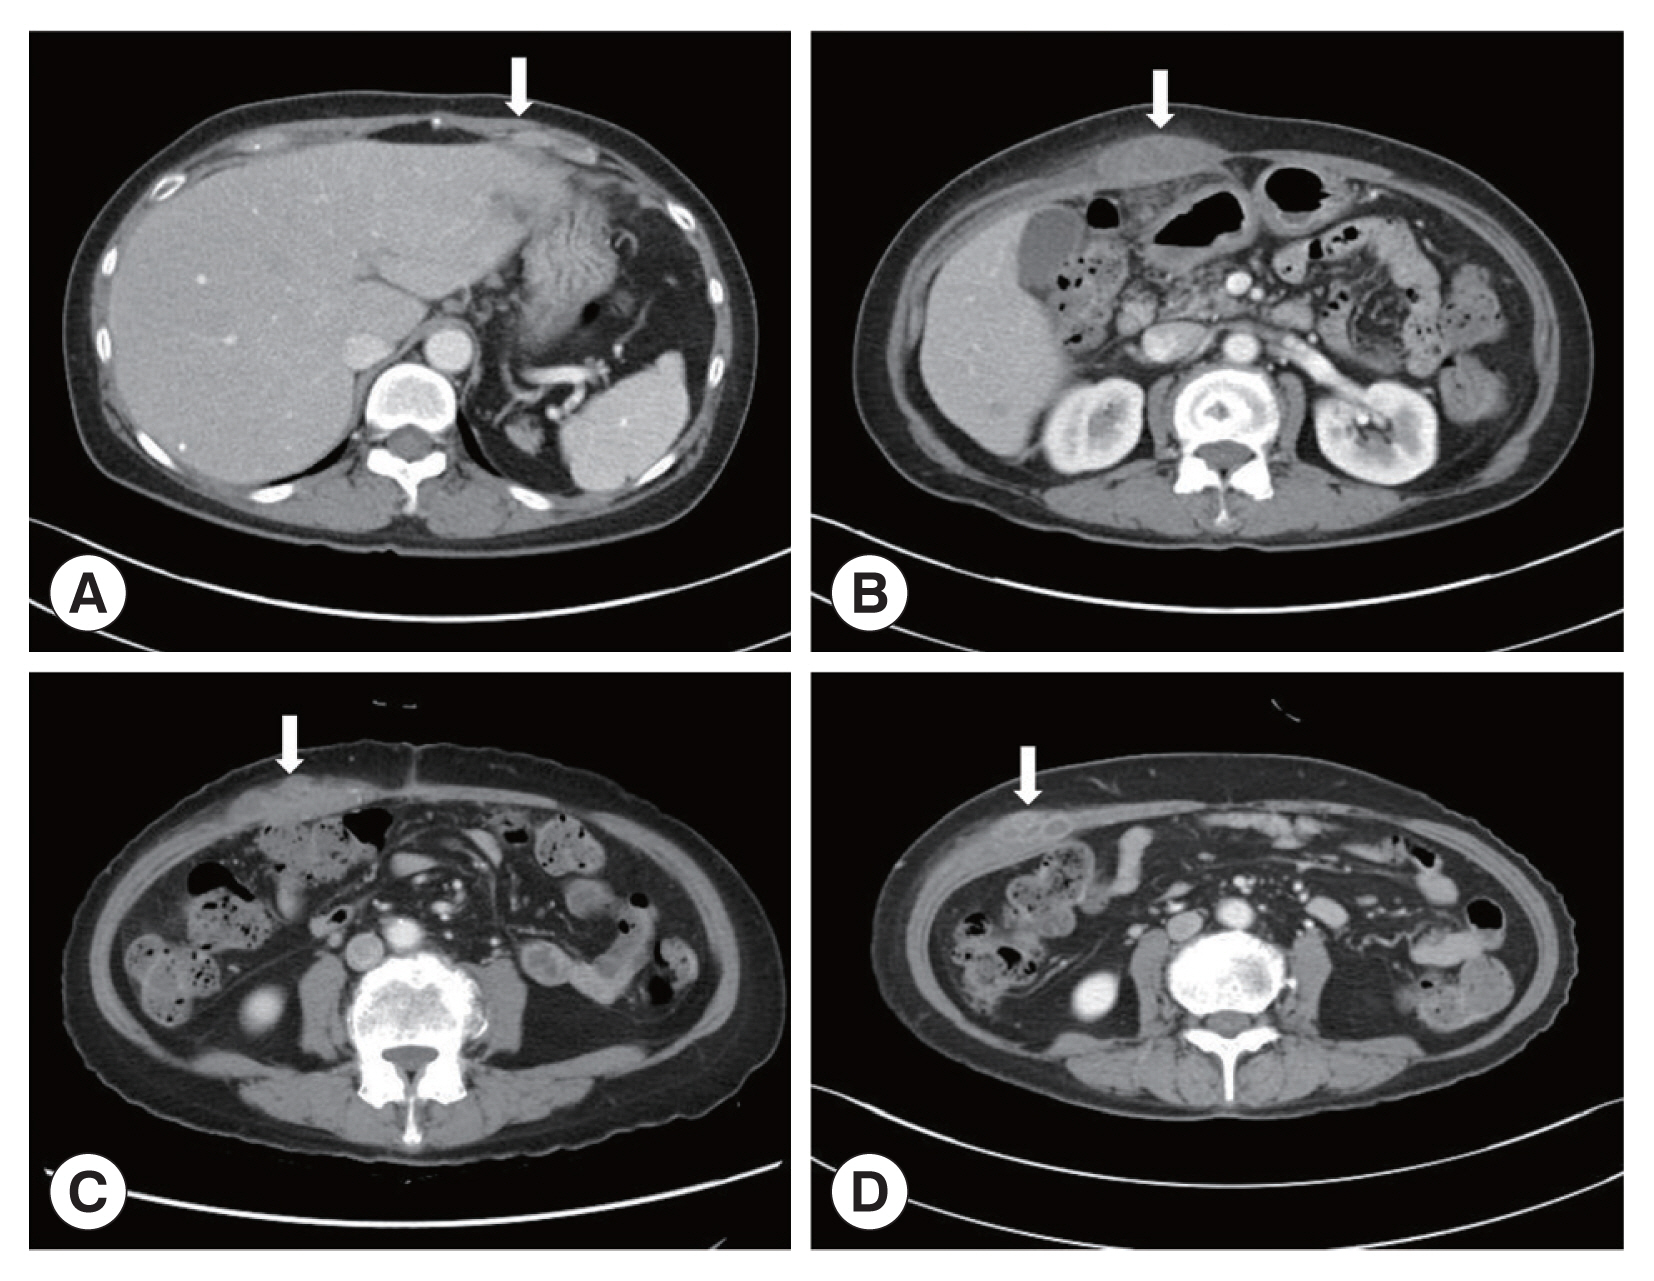

A 66-year-old Korean woman living in Pusan visited the Pusan National University Hospital on July 11, 2021, with an abdominal mass. She had been suffered from hypothyroidism. In June 2021, she was diagnosed with a hepatic abscess by computed tomography (CT) performed during an evaluation of RUQ pain at another hospital. The symptoms improved by symptomatic treatment and she was discharged after administration of antibiotics (ceftriaxone and metronidazole) (Fig. 1A). She visited again our hospital due to recurrence of the RUQ pain. The mass was palpable in the abdominal cavity, we checked the mas with CT. Some swelling and cell infiltration was confirmed, and parasitic infection was suspected (Fig. 1B). She received praziquantel (25 mg/kg 3 days). Most fascioliasis patients showed eosinophilia and abdominal distension [11]. Abdominal distension along with eosinophilia was also confirmed in this patient. In August 2021, liver abscess was percutaneously drained, after which she was discharged. However, she complained of new pain in the subcostal region (Fig. 1C). Praziquantel treatment were maintained, but her symptoms did not improve. New multiple abscesses were found below the previous lesion on abdominal CT. Compared to the previous CT, a lateral movement of the abscess was observed with maximum size of 3.4 cm (Fig. 1D). The CT showed abdominal distension. The laboratory test showed eosinophilia (7.3%, normal range 0–6.9%) with low number of segmented neutrophil (38.8%, normal range 40.0–70.4%). The mean corpuscular hemoglobin concentration, eosinophil count, and erythrocyte sedimentation rate increased, and the levels of seg neutrophils decreased. A biopsy revealed a leave-like parasite. The length was approximately 1.7–1.8-long, and the width was 0.5–0.8-long. The morphology of the posterior testis of the F. hepatica was observed under a microscope. The fluke did not have hooks or spines but were characterized by suckers. The acetabulum wis located at the anterior part of the worm (Fig. 2A). The granuloma contained acute and chronic inflammatory reactions accompanied by numerous eosinophilic invasive micronecrosis.